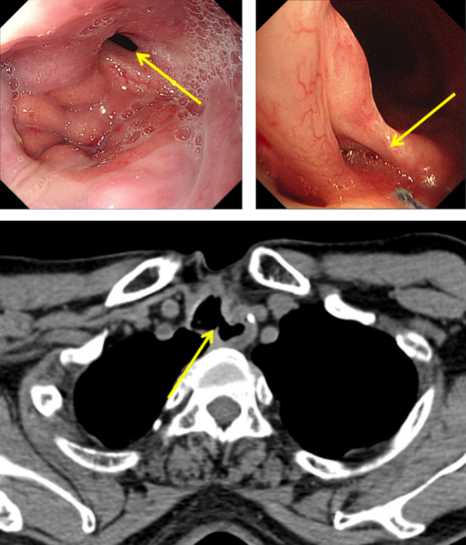

圖1:氣管食管瘺口

經(jīng)推薦,老秦慕名來(lái)到我院胸外科胡楊副主任醫(yī)師處就診。經(jīng)檢查發(fā)現(xiàn),老秦的病情與其他氣管食管瘺患者相比,更為復(fù)雜和嚴(yán)重:一是瘺口所處位置較為“刁鉆”。患者氣管食管間瘺口位于頸胸交界部位,無(wú)論是從頸部或是胸部入路均難以充分暴露瘺口;二是瘺口情況較為糟糕。該患者于外院多次行瘺口修補(bǔ)手術(shù),瘺口附近勢(shì)必粘連嚴(yán)重、組織結(jié)構(gòu)難以辨認(rèn),損傷喉返神經(jīng)、頸胸部血管等重要結(jié)構(gòu)的風(fēng)險(xiǎn)高;組織血供破壞嚴(yán)重,術(shù)后缺血壞死風(fēng)險(xiǎn)高;三是患者營(yíng)養(yǎng)嚴(yán)重不足。該患者由于“氣管食管瘺”已兩年未經(jīng)口進(jìn)食,身體非常虛弱。